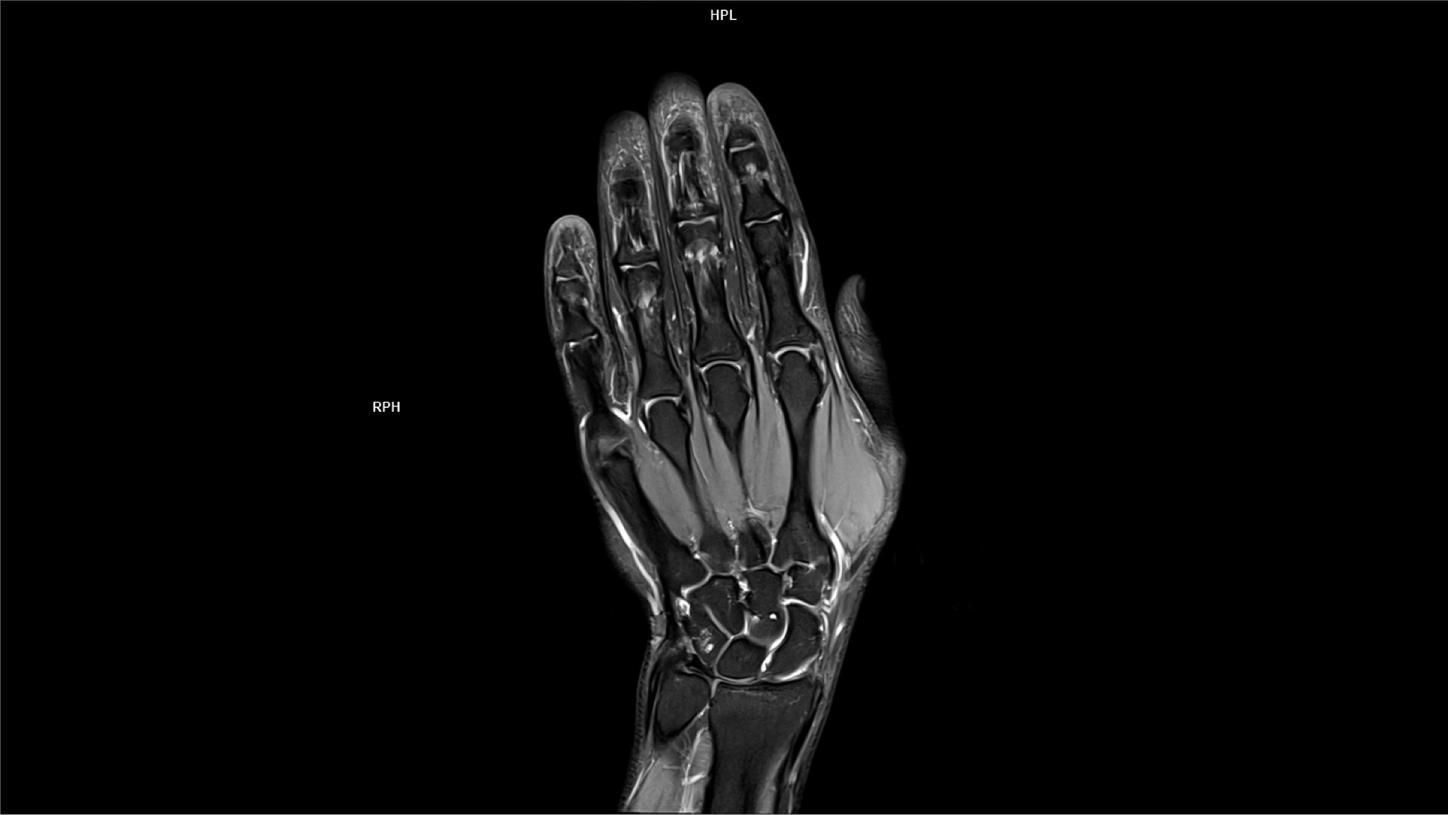

PD Cor FS DR Boost High Resolution-MAGNETOM Lumina

Coil-Hand Wrist 16/Resolution-.2 X .2 X 2/Scan Time-1:44/Aceleration-p3